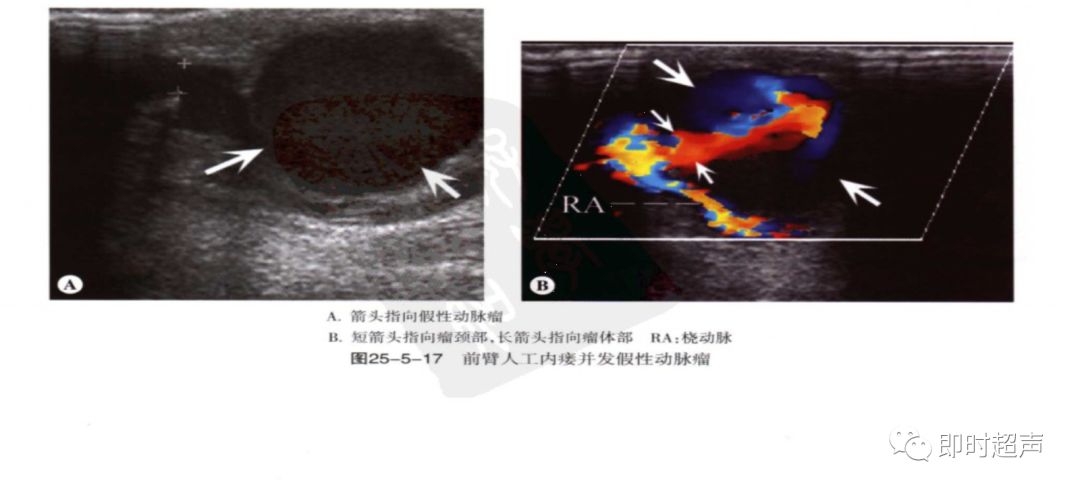

动脉瘤及静脉瘤样扩张